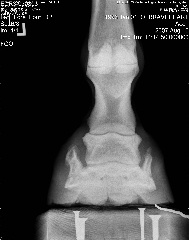

Posted on Friday, Aug 10, 2007 - 6:54 pm: We can trot on straight lines! Vet said he's at the limit from the coffin bone to the wall, that's not good, but he said he thought his angles looked ok. He thought that since the fetlock joints were off, he'd need more wall on the ;left front inside and more wall on the right front on the outside, then that should fix that. He said he'd like to see more sole, but he hooftested him and said his feet are rock hard so that should not be a worry for now. He's going to compare these to December's xrays and call. But based on what little he saw on the xrays and how he moved on the lunge, he said as long as I ride him in boots he should be just fine Here's a link to the xrays: https://s141.photobucket.com/albums/r59/wishes_album/xrays%20aug%2007/ Here are smaller versions: LF Lateral LF DP RF Lateral RF DP Edited to add that he was shocked that he could feel ribs when he asked Brave to move over But yes, he still is on a strict diet.

|

Posted on Friday, Aug 10, 2007 - 7:32 pm: Dr. O or anyone, Do his heels need to be lowered? I find it odd asking this question, but based on the xrays...Thanks! |

Posted on Friday, Aug 10, 2007 - 8:10 pm: Well, you can see from the laterals, his heels don't need to be higher. Are they back to the widest point of the frog? Breakover still looks too far forward to me if it's indicated by the white contrast line, but perhaps that's an illusion? |

Posted on Friday, Aug 10, 2007 - 9:27 pm: and this from the vet that was extremely resistant to your going barefoot? to the point that you were afraid he'd DrOp you if you did?...hmmmmmmm.....i think you're heading in the right direction with his feet..breakover still needs to come back a tad, as well as the heel.. remmeber that the widest part of the foot should be at about the halfway point... his is farther back than that... that makes the breakover too far forward.. but they look tougher than ever and am so glad you've been given the ok to ride some... congrats and have fun!!! |